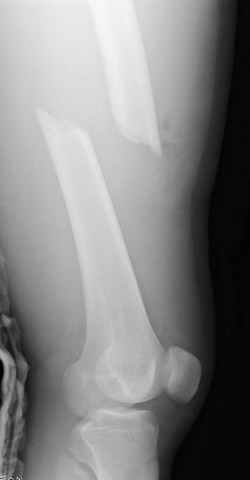

больному 42, автоавария, политравма, открытая черепномозговая травма, безсознании, открытый перелом бедра, размозжение мягких тканей, дефект кожи на передней поверхности бедра около 13 см2 от ожога, компартмент синдром.

По поводу открытого перелома больной ургентно взят на ретроградное интрамедулярное штифтование, после рутинного дебрайдмента и фасциотомии на бедре и на голени.

перелом бедра

постоперационные